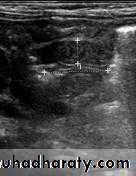

Epidemiology:-Pyloric stenosis is relatively common and has a male predilection (M:F ~ 4:1), and is more commonly seen in Caucasians 4.

It typically occurs between the 4-8 weeks of life. There may be a positive family history.

Incidence of hypertrophic pyloric stenosis is approximately 2-5 per 1,000 births per year in most white populations.

In a normal situation, the pyloric muscle thickness (diameter of a single muscular wall on a transverse image) should normally be less than 3 mm (most accurate 3) and the length (longitudinal measurement) should not exceed 15 mm.